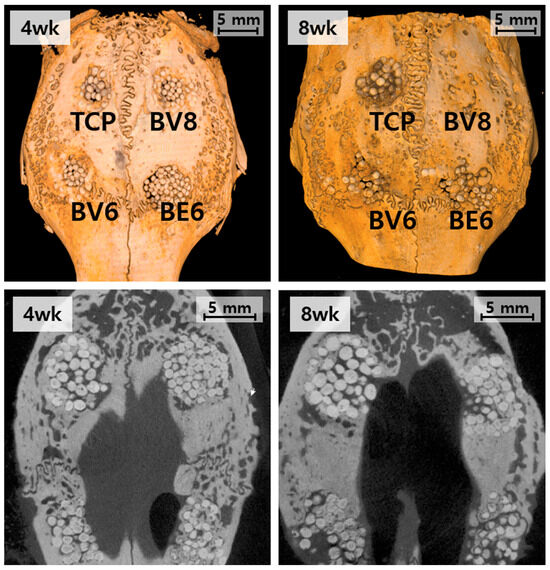

3.3.2. Micro-CT Analysis at 8 Weeks Post-Implantation